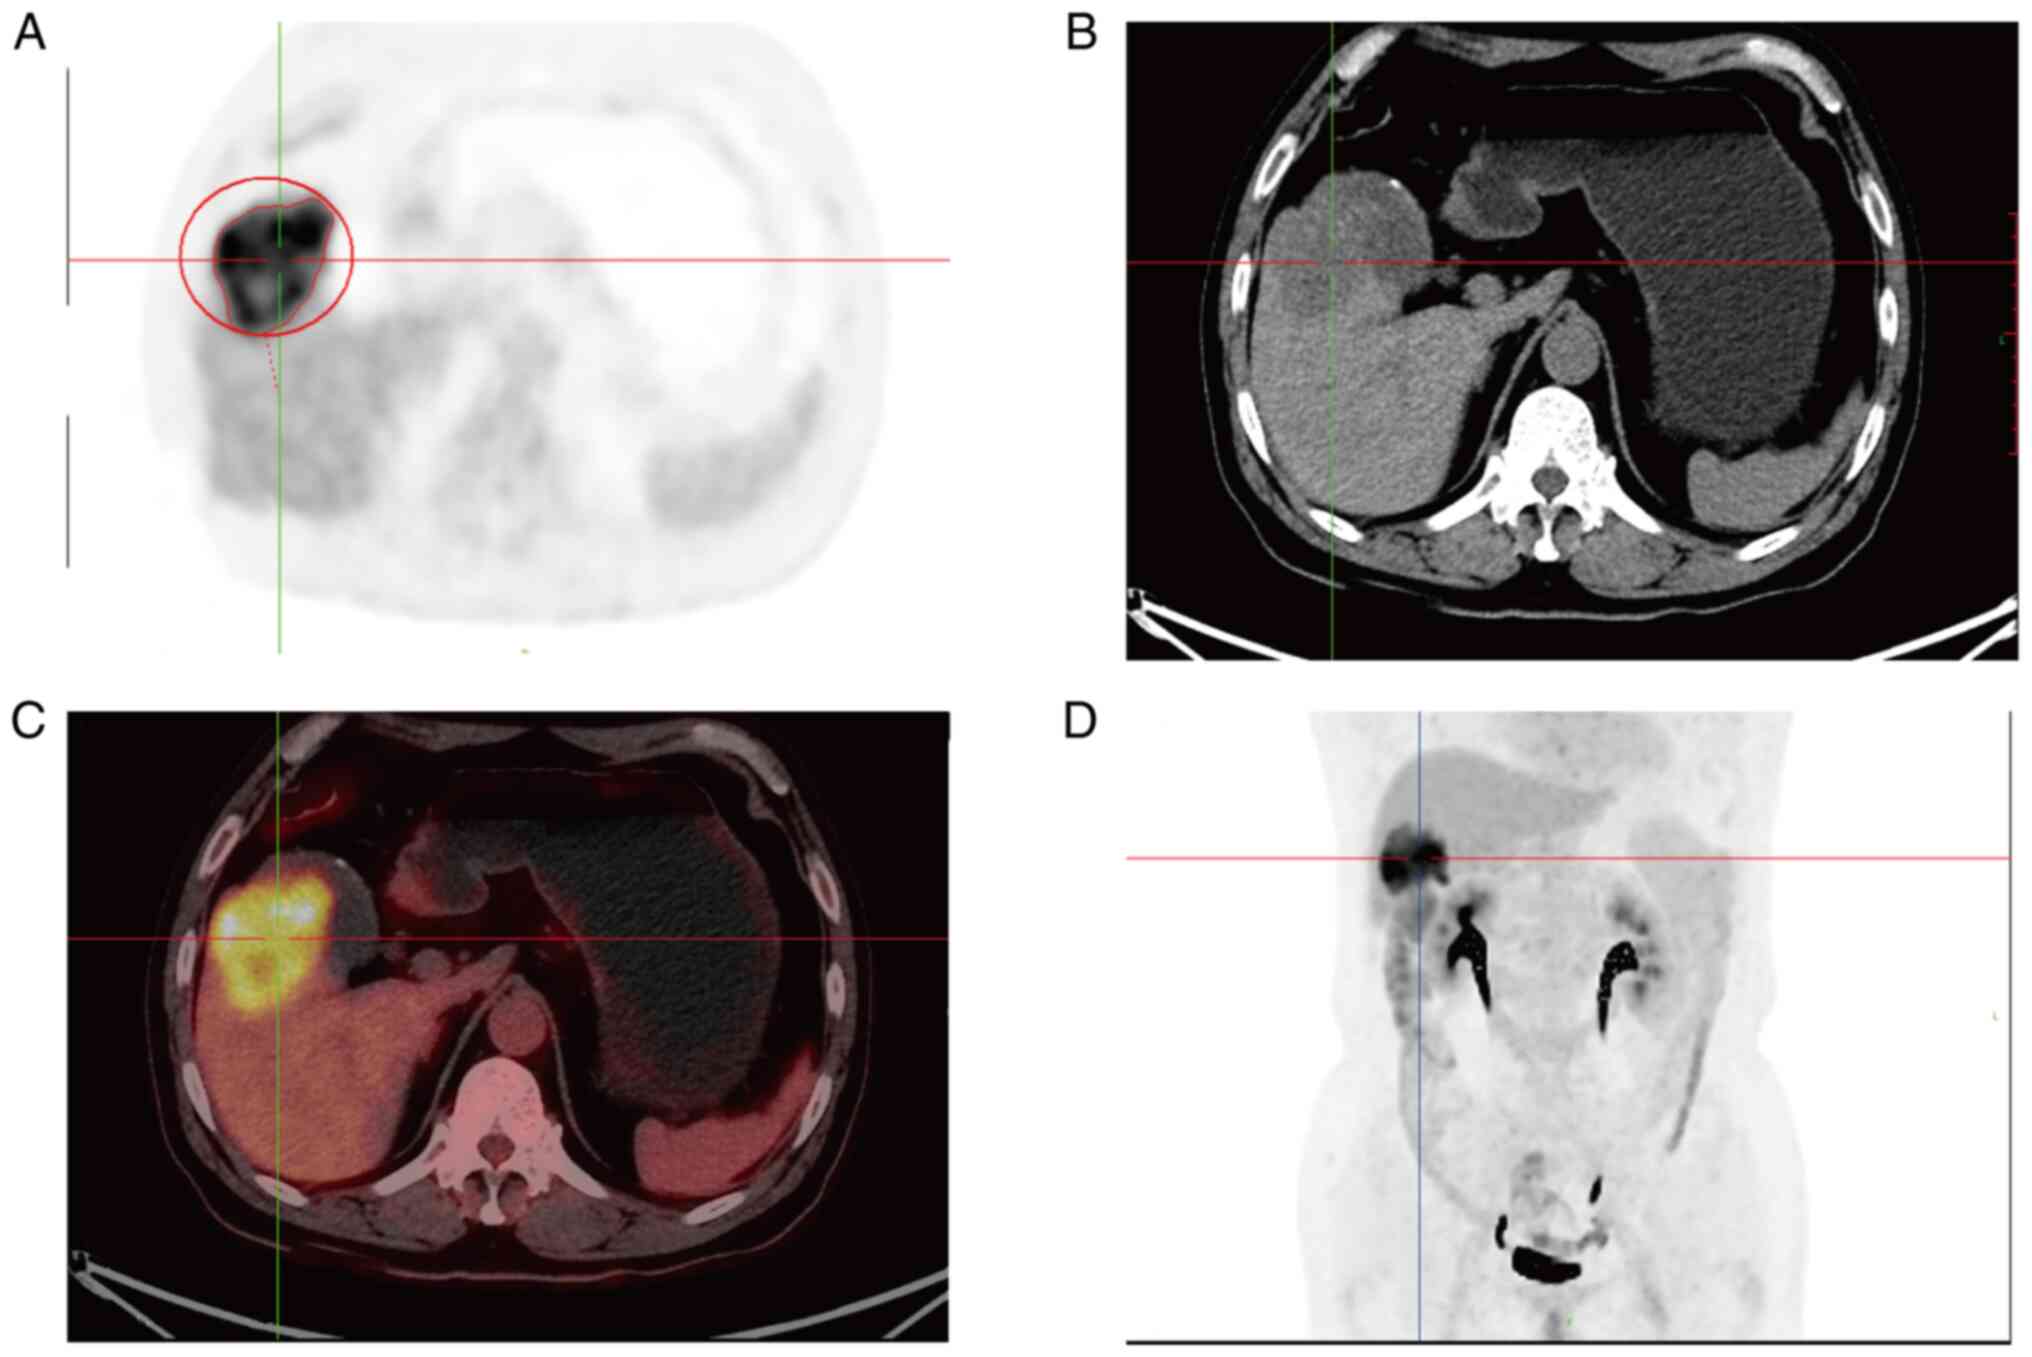

Figure 2.

Chest and abdominal PET/CT images of case 1. (A) PET imaging 1 h after FDG injection. (B) CT imaging 1 h after FDG tracer injection. (C) 1 h after injection of FDG tracer, PET/CT fusion imaging. (D) Maximum intensity projection. PET/CT, peoperative positron emission tomography/computed tomography; FDG, fluorodeoxyglucose.

The case was a 65-year-old male patient with no family history of cancer and with a past medical history of appendectomy and surgery for lumbar disc herniation. Suspected gallbladder malignancy was found during physical examination. He had no fever, abdominal pain, nausea, vomiting, weight loss and other complaints. No abnormal clinical signs were detected by abdominal examination. Computed tomography (CT) scanning of upper abdomen indicated soft tissue shadows could be seen at the bottom of the gallbladder, invading the liver, and the boundary was blurred. In addition, a cyst was found in the left lobe of liver. Contrast-enhanced CT scanning indicated significant uneven enhancement and it was about 60×45 mm in size (Fig. 1). Preoperative positron emission tomography/computed tomography (PET/CT) showed irregular soft tissue occupancy at the bottom of the gallbladder with abnormally high metabolic activity and low-density occupancy in the lower right anterior lobe with abnormally inhomogeneity high metabolic activity (Fig. 2). Levels of tumor markers were shown in Table I. All these results suggested that gallbladder malignant lesions with the right liver lobe involvement. CT provided no clear evidence of distal metastases.